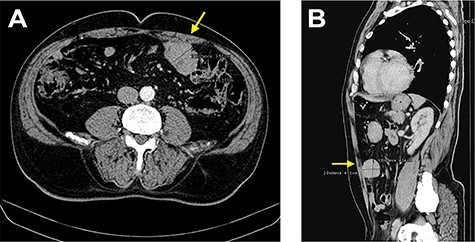

The staging computed tomography (CT) revealed a ‘nodular image with 48 × 57 × 44 mm, close to the anterior abdominal wall’ (Fig. 1) with active bleeding, two non-specific nodules in the left lung and five in the right lung, all infracentimetric.

CT images showing a nodular lesion with 48 × 57 × 44 mm, close to the anterior abdominal wall (yellow arrow).